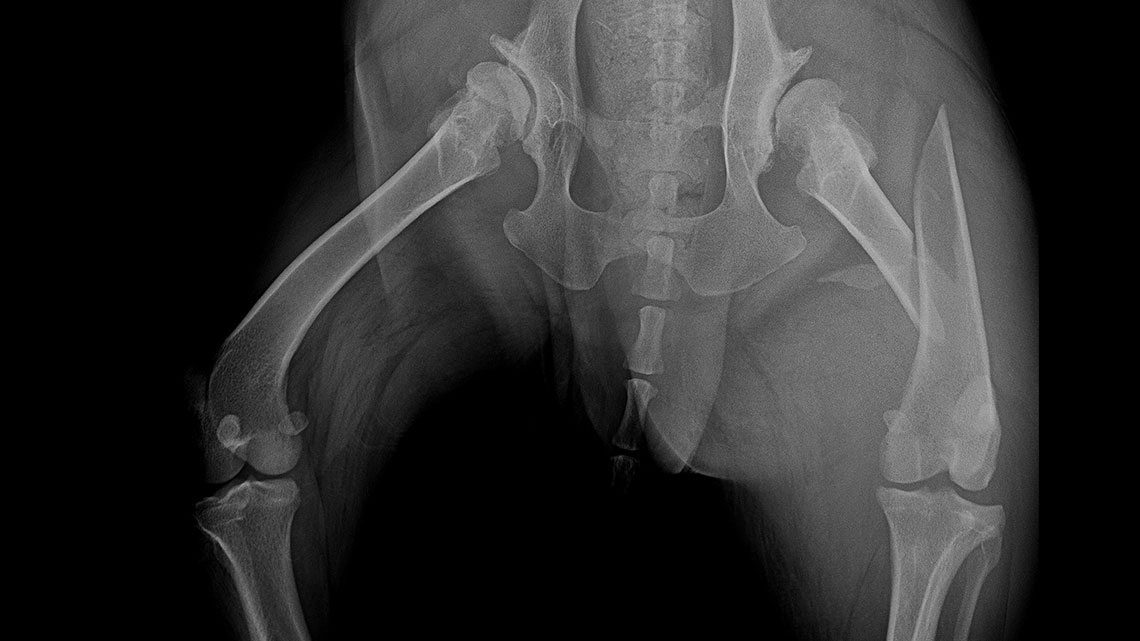

In our case, a 10-year-old labrador is involved in a car accident and his left femur and right tibia are severely injured. The dog had difficulty moving anyway due to severe hip arthrosis. During one surgical narcosis, K-pin - polyaxial locking plating was applied to both bones, the larger fragments were also fixed with 1-1 lag screws.